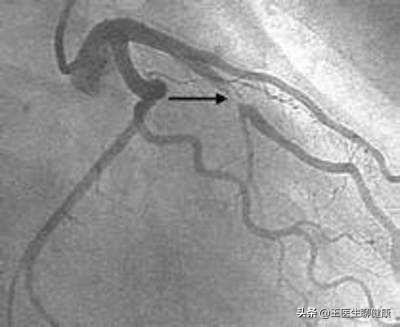

Comme le montre la figure, la zone de marquage de la tête d'écrêtage est environ 40 % plus étroite.

2, les résultats de l'imagerie montrent que le degré de sténose de la lésion de l'artère coronaire est compris entre 50 et 70 % : dans ce cas, le stent fait partie des lésions critiques qui peuvent être posées ou non, et il doit être analysé au cas par cas. Si le patient présente des symptômes clairs d'angine de poitrine, tels que des douleurs thoraciques pendant les activités, chacune durant environ 5 minutes, qui peuvent être soulagées après le repos, et que la nitroglycérine est efficace, la pose d'un stent est également recommandée pour ces patients. Si les patients ne présentent pas de symptômes clairs d'angine de poitrine, ils peuvent être traités de manière conservatrice avec des médicaments, tels que l'aspirine orale, le métoprolol et les statines. Une approche plus fiable consiste à effectuer une autre échographie coronaire (IVUS) ou une tomographie optique intracoronaire (OCT), qui sont des examens d'imagerie intravasculaire et peuvent aider à analyser la valeur précise du degré de sténose. Si la sténose atteint 70 % à l'issue de ces deux examens, la pose d'une endoprothèse est toujours recommandée.